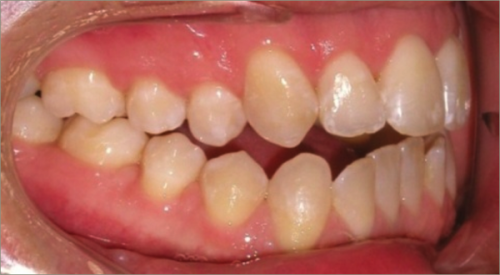

30 year old male:

Diagnosis:

- Upper and lower crowding

- Narrow upper & lowerarch forms

- Open bite

Treatment:

- Invisalign

- Non-Extraction

- 27 months